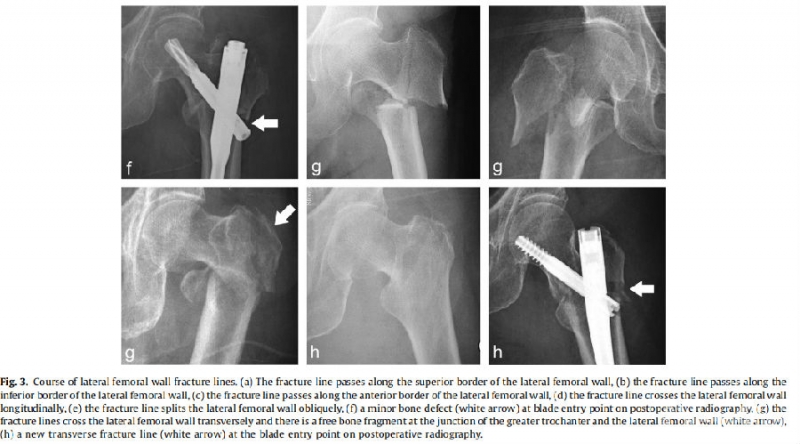

图3. 外侧壁横行骨折线示意图(白色箭头)

结果:10例(10%)发生内固定失败。单因素分析发现大转子和外侧壁连接处存在游离骨块(21.25;95%CI,4.31-104.67;p<0.001)和外侧壁的横行骨折线(原发或医源性)(OR, 5.36;95%CI,1.29-22.30;p=0.021)为内固定失败的危险因素。多因素回归分析发现,大转子和外侧壁连接处存在游离骨块(OR,16.05;95%CI,3.06-84.23;p= 0.001)是内固定失败的危险因素。

结论:股骨大转子与外侧壁交界处存在游离骨块和外侧壁横行骨折线是股骨转子间骨折伴外侧壁骨折内固定失败的危险因素。股骨外侧壁的完整性与股骨转子间骨折的预后相关。股骨转子间骨折合并外侧壁骨折时,可能需要重建股骨外侧壁。